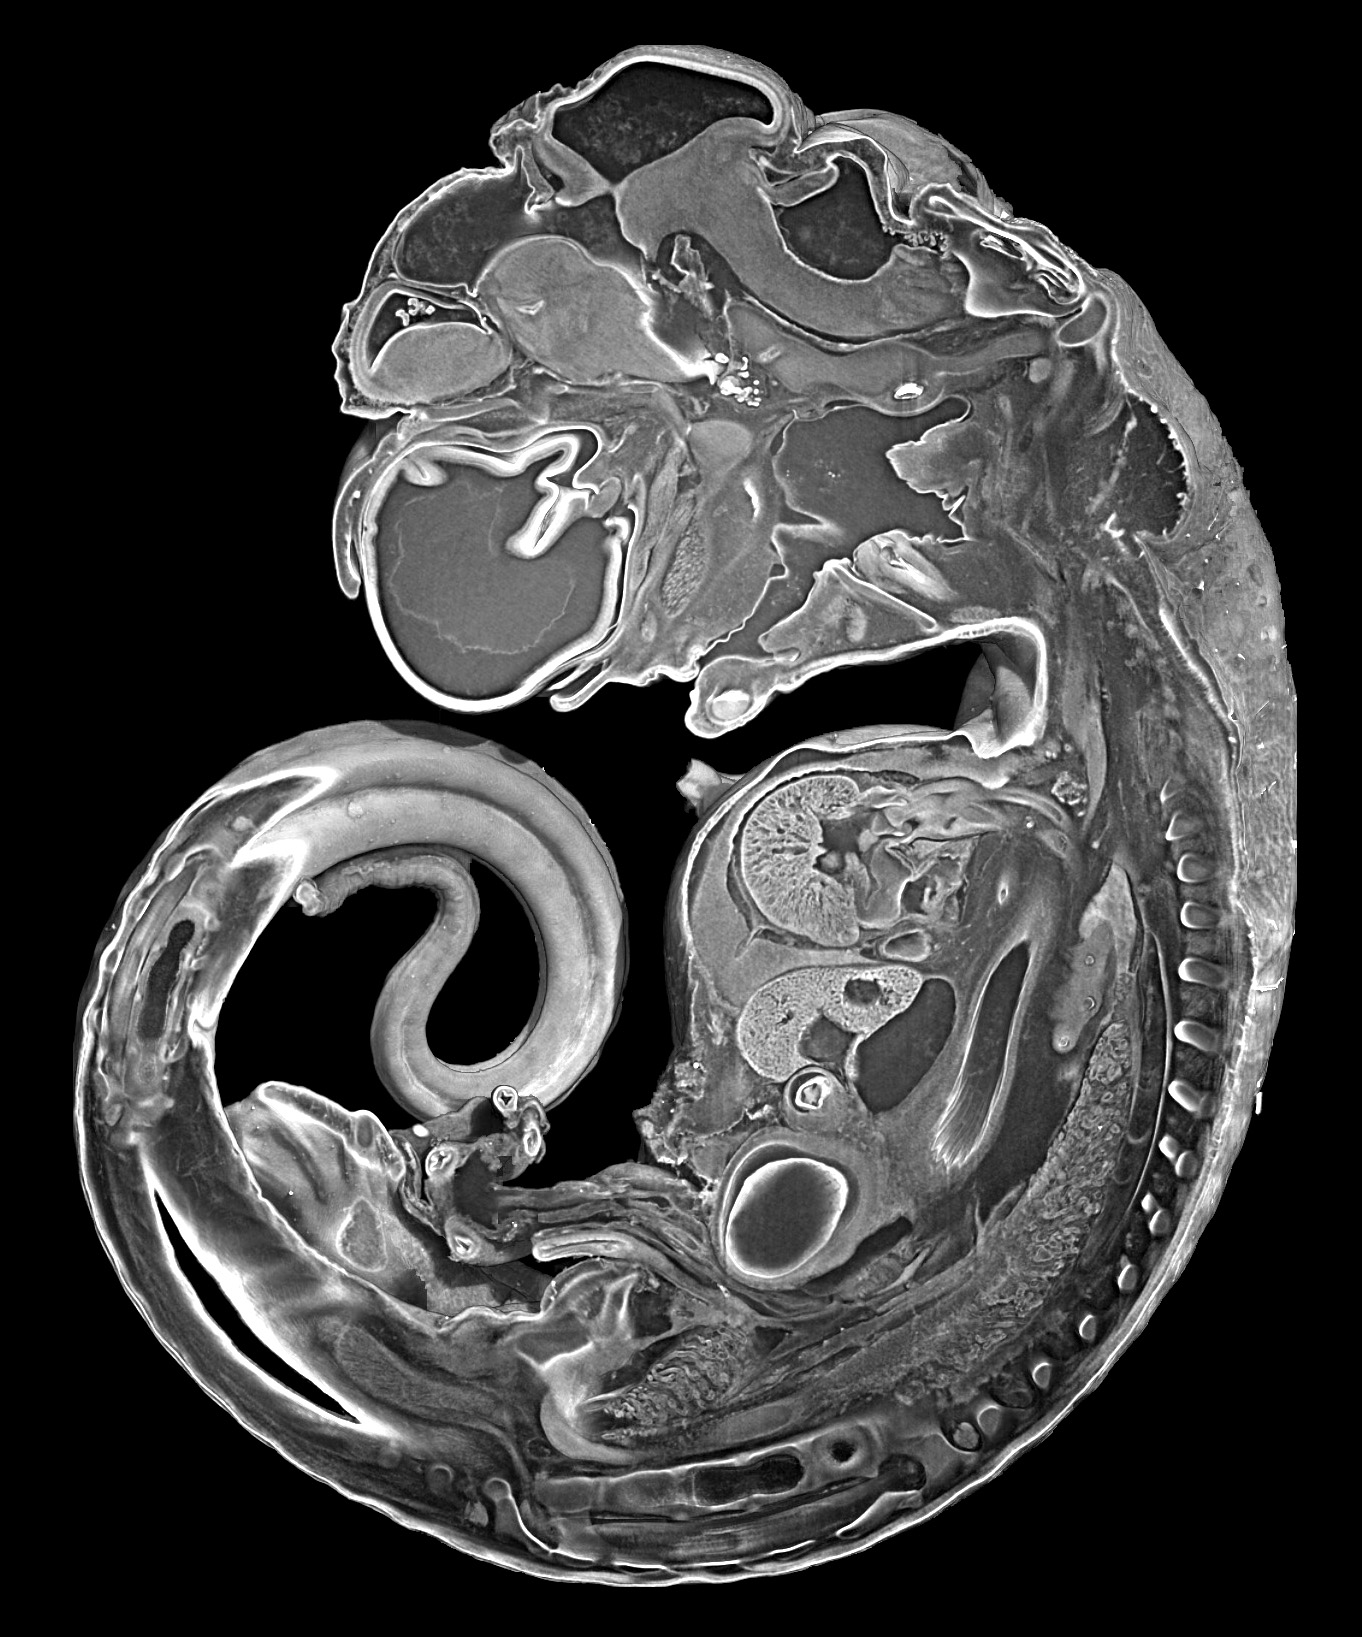

27-29 krokodil